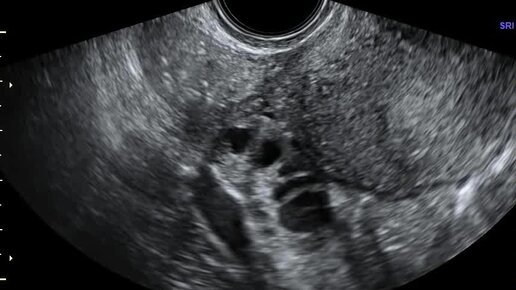

Видео: Поперечное сканирование матки. Правый яичник расположен по заднебоковой поверхности матки. Спаечный процесс